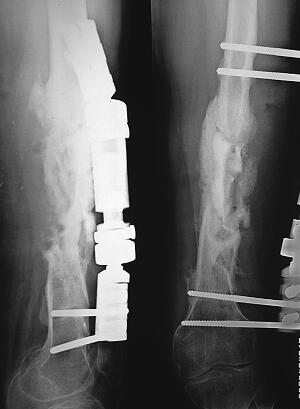

完善各项常规检查,无明显手术禁忌证,停止使用抗生素3天后,取标本进行细菌培养,结果表明产ESBL肺炎克雷伯菌生长,敏感抗生素为亚胺培南;住院5天时,在硬膜外阻滞麻醉下,行清创、含万古霉素的人工骨浆填充骨缺损术。手术步骤:沿原切口切开,梭形切除切口线上的窦道,术中见骨块间大量脓性物,除前外的部分骨块与软组织相连,其余十多块游离骨折片均呈枯黄或枯白色,清除脓性物,死骨间系纤维性增生组织连接。彻底清除所有死骨、炎性增生组织,尤其是髓内增生组织,不做髓腔再通;对于非切口线上的窦道逐一搔刮。然后,使用大量生理盐水、双氧水交替脉压冲洗,再使用含广谱抗生素的生理盐水冲洗,最后稀释的碘伏液浸泡10分钟。重新消毒后,铺巾;更换无菌手术器械,术者更换手套。将含万古霉素的人工骨浆填充骨缺损处,完全封闭清创后所形成的死腔,以避免术后空腔积液。留置持续冲洗引流管,逐层关闭切口。术后1天拍摄X线片如图4;术后3天时体温恢复正常,WBC为0.8×1012,ESR降至31mm/h;使用亚胺培南2周,持续灌注冲洗5天,冲洗液无混浊物时停止冲洗,仍留置引流管以维持引流状态,2天后引流管内无渗出时拔除引流管;同时辅以中药内服,组方为复元活血汤与五味消毒饮加减,每天一剂。术后2周时切口愈合,四周出院,嘱其继续服用中药4个月后复查。术后4个月复查时,右大腿无明显肿痛,肤温正常,感染窦道无复发,血常规与血沉正常,故再次住院,拍摄X线片示固定钉轻微松动,股骨骨折处后、内侧已有连续性骨痂生长。行自体髂骨植入术;术中见骨折处无脓性物,股骨骨折的后内侧达骨性愈合,取深层组织再次进行细菌培养,彻底清除前外侧骨缺损处增生组织,见骨缺损处骨质渗血良好。将自体髂骨修成细骨条,与头孢他啶2.0g混合,紧密填充于骨缺损处。细菌培养结果表明无细菌生长;2周常规出院。内服三七接骨丸(我院内部制剂)3个月。再次手术后4个月随访结果:右侧髋关节功能恢复正常,膝关节僵直,无感染复发,X线片示骨折已愈合,门诊拆除固定支架,嘱其行膝关节松解术,但病人未复诊。

图4 第2次手术X线片